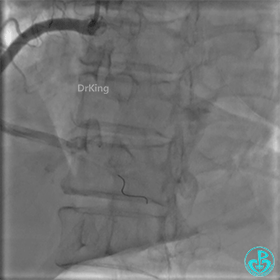

急诊冠脉造影

PL分支开口闭塞,PD分支血流3级,开口处可见血栓。

通过造影导管右冠脉内推注10mg尿激酶原溶栓。

更换6F JR 4.0指引导管,Runthrough NS进入PL分支。

2.0×15mm球囊扩张PL分支开口后PL恢复2级血流。

PL远端血管周围似乎有片状造影剂滞留。